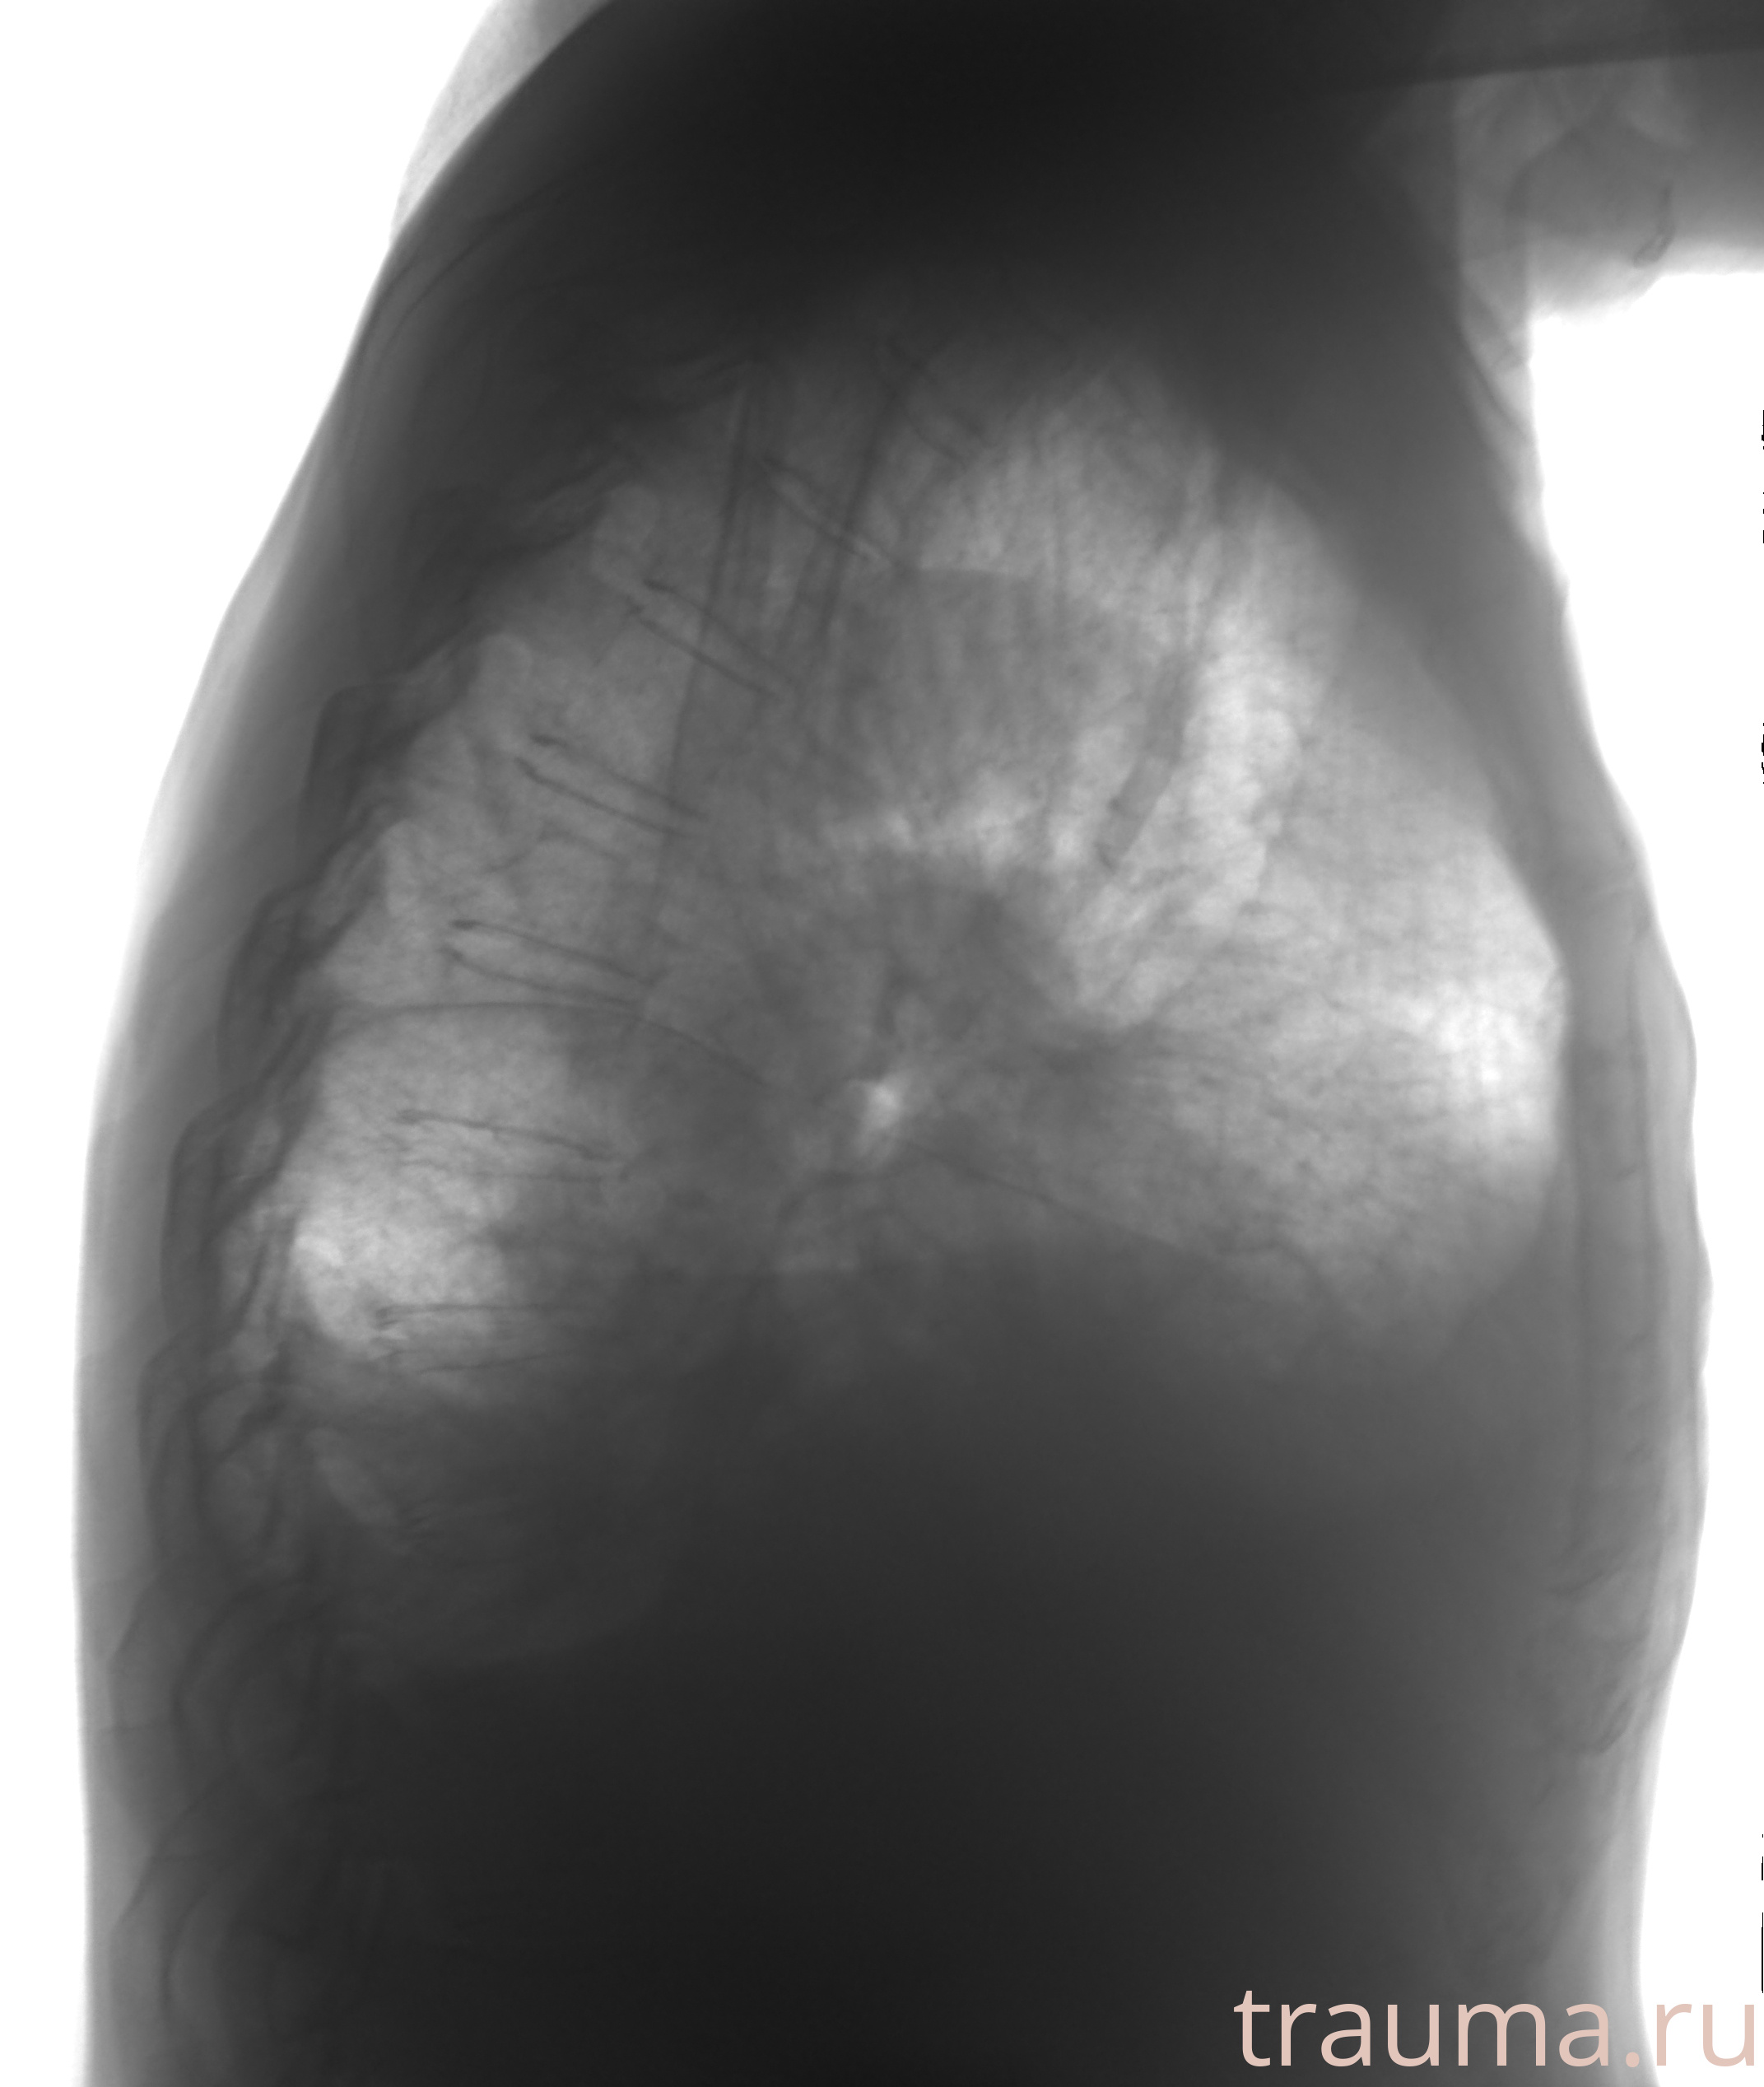

Рентгенограммы

Рентген на дому: по вашему адресу приезжает врач-рентгенолог, травматолог-ортопед с мобильным рентгеновским аппаратом, проводит диагностику травмы или заболевания, делает необходимые рентгенограммы, дает рекомендации по дальнейшему лечению. Получить качественные снимки в домашних условиях возможно благодаря уникальной методике, разработанной МосРентген Центром для института  Склифосовского

при переломе шейки бедра и пневмонии от компании МосРентген Центр - партнера Института имени Склифосовского